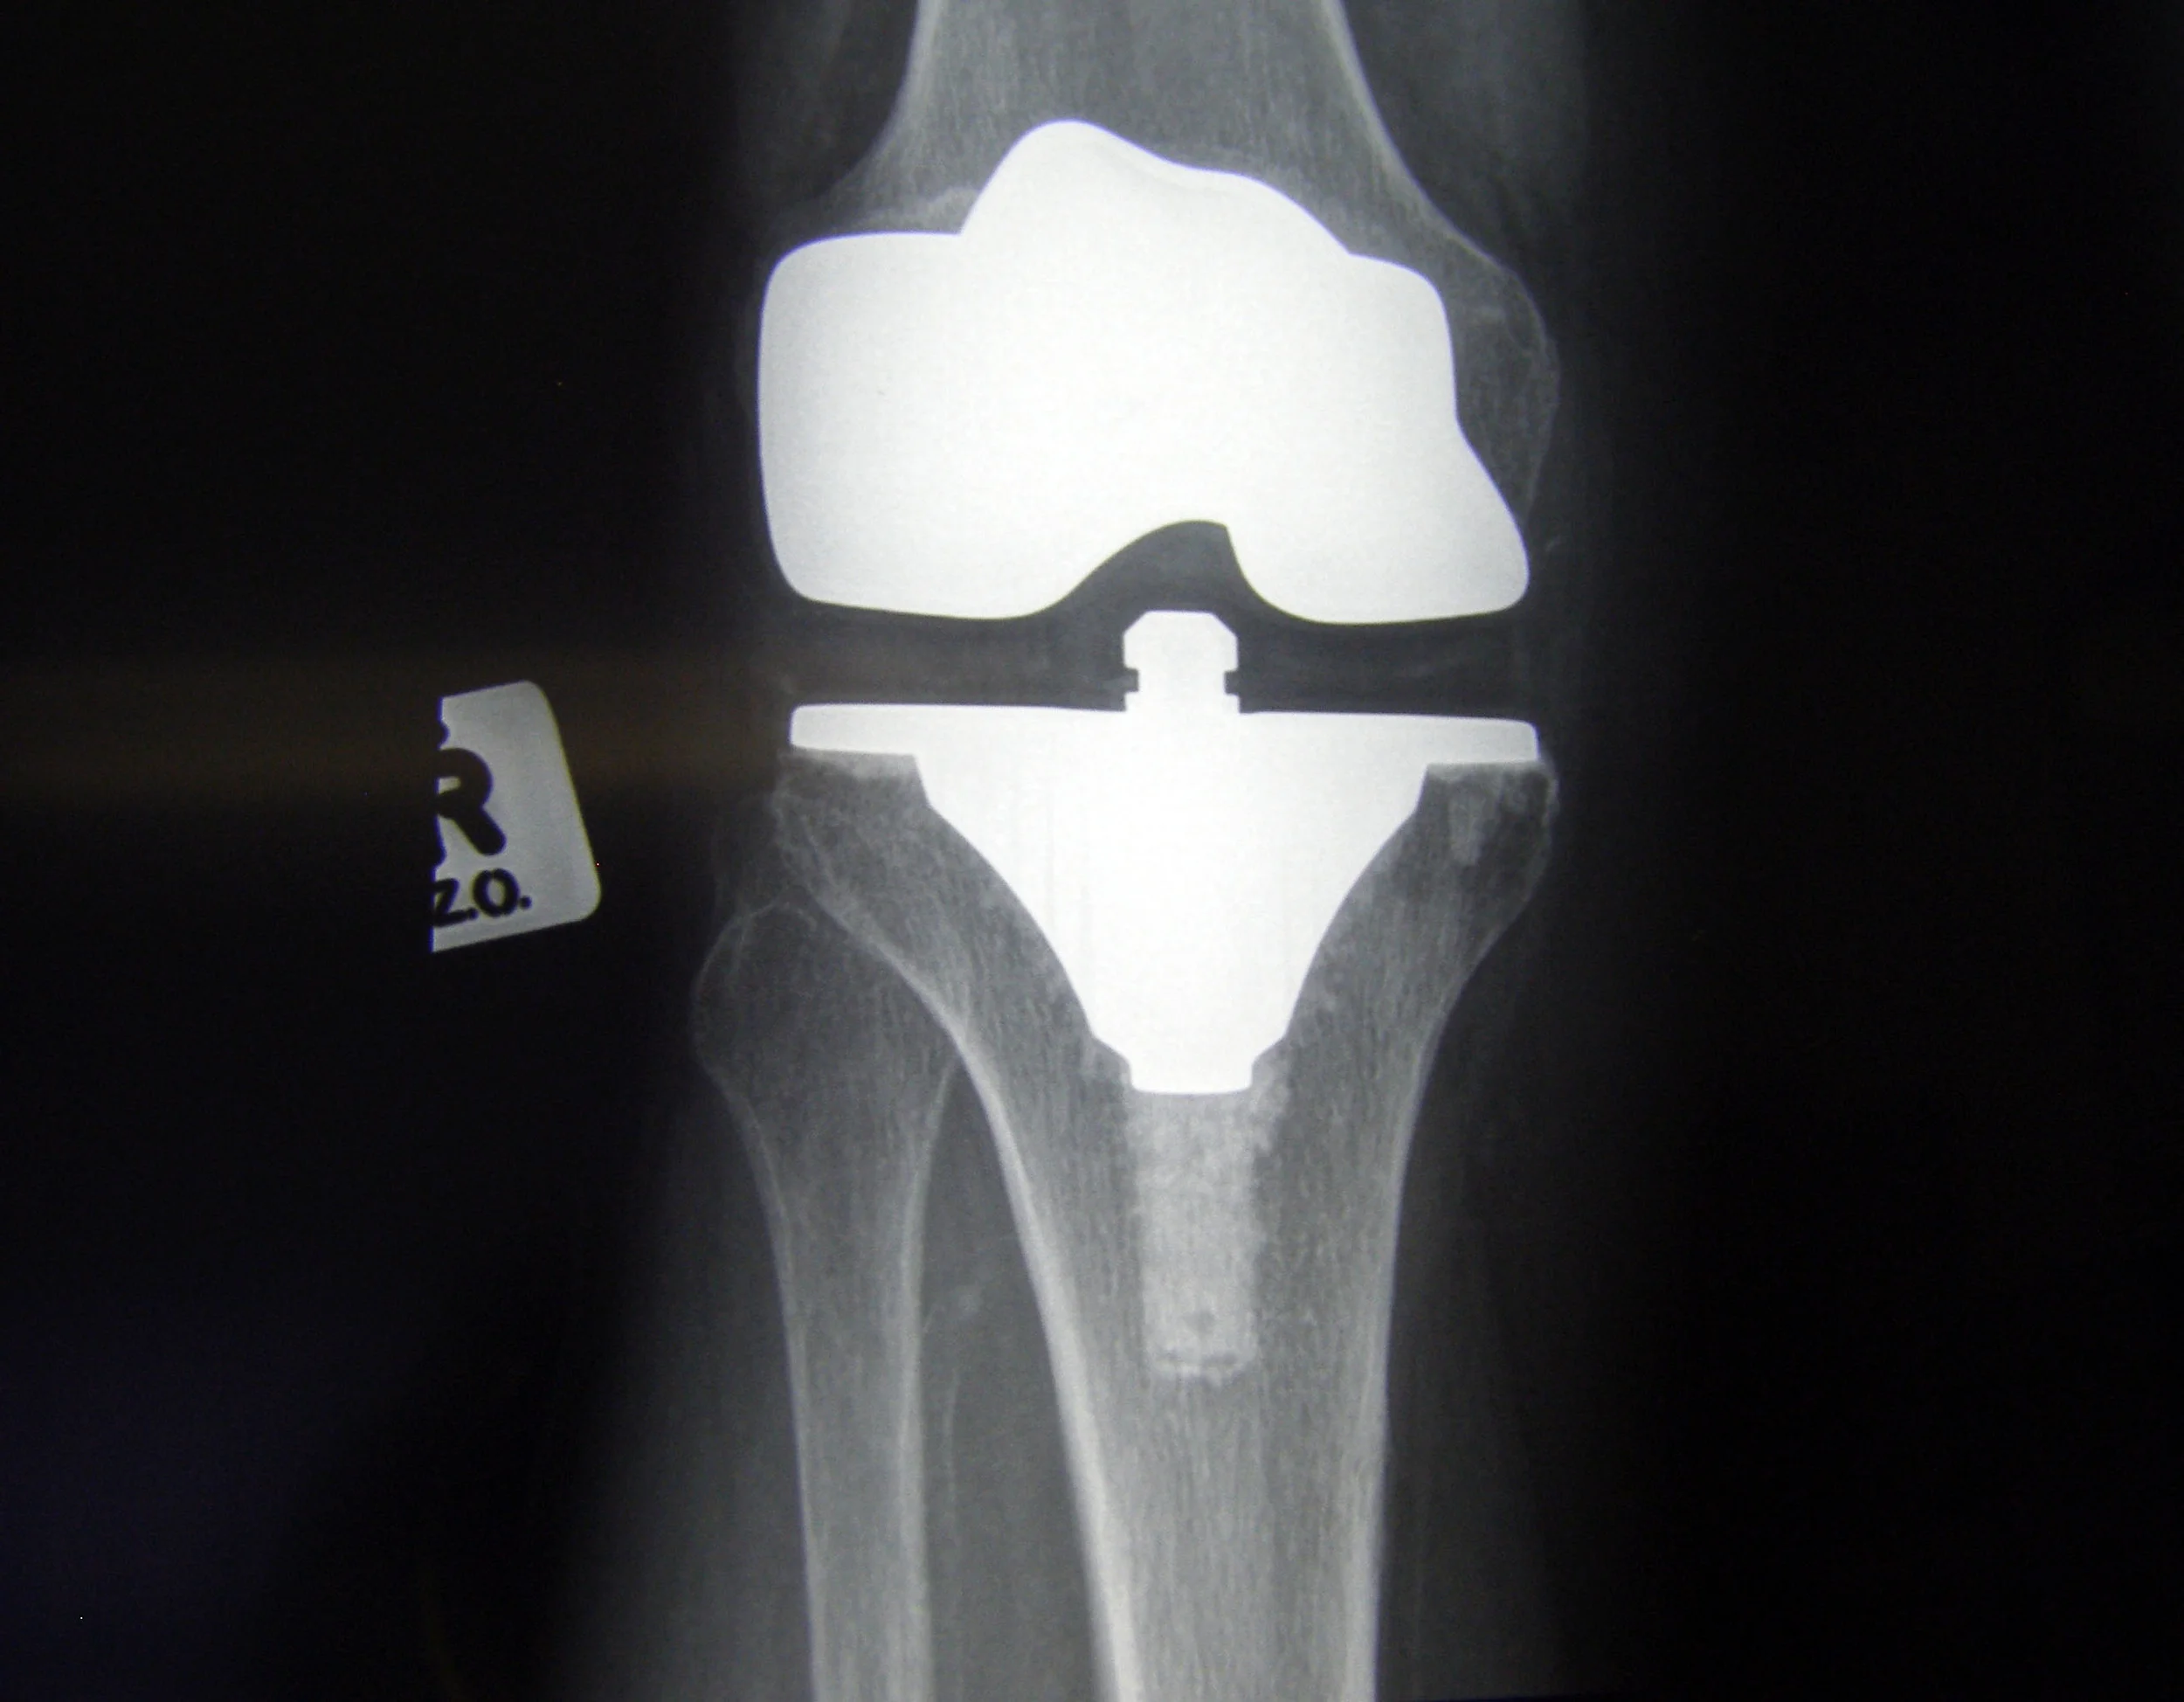

Then, one summer, I tore my medial collateral ligament (MCL). I remember the day vividly; it’s become one of the few memories that I can recall with all five senses. One minute I was playing basketball, jumping to get a rebound, and the next I was on the concrete, screaming in pain while clutching my deformed left knee.

I remember the doctor telling me that I’d be unable to play sports for at least six months and would need regular physiotherapy sessions, and possibly surgery, if I ever hoped to fully heal. When he delivered the news, I thought, what now?